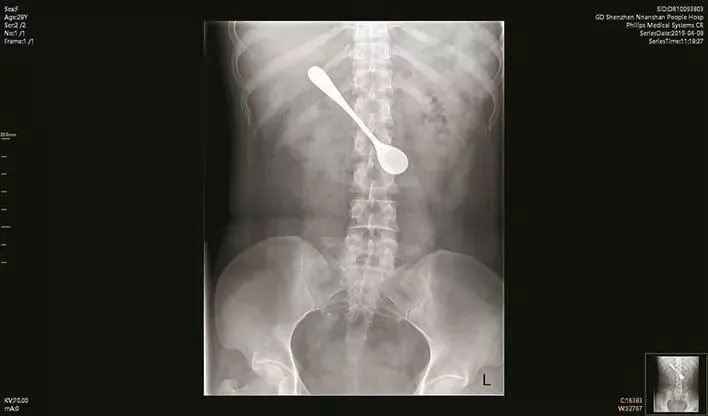

(หญิงสาวเผลอกลืนช้อนลงคอ จนไปติดอยู่ในลำไส้ Photo credit: Pear Video)

หมอและทีมผ่าตัดโรงพยาบาลเชินเจิ้นในจีน ต้องเข็นคนไข้สาวรายหนึ่ง ทราบชื่อว่าลิลลี่ เข้าห้องผ่าตัดฉุกเฉินเพืื่อผ่าเอาช้อนเหล็กยาว 13 ซม. ออกมาจากลำไส้เล็กส่วนต้นของเธอ หลังเธอเผลอกลืนมันลงไปขณะพยายามเขี่ยเอาก้างปลาที่ติดคอเธอออก เหตุดังกล่าวเกิดขึ้นช่วงเทศกาลเช็งเม้งที่ผ่านมา

ลิลลี่เล่าว่าเธอรู้สึกเหมือนมีก้างปลาติดคออยู่ เลยเอาช้อนล้วงเข้าไปจะเขี่ยออก จนเผลอกลืนช้อนลงไปด้วย แต่กระนั้นเธอก็ยังไม่ยอมไปหาหมอ เพราะเห็นว่าไม่ได้รู้สึกปวดท้องอะไรเลยปล่อยไปแบบนั้น บวกกับใกล้จะเช็งเม้งแล้วด้วย เธอจึงปล่อยไว้อย่างนั้นนาน 4 วัน กว่าจะไปพบหมอและเอ็กซเรย์ดู จนเห็นช้อนสแตนเลสดังกล่าวในท้องของเธอได้อย่างชัดเจน

ดร. ซุน ถิงจี หมอผู้รับผิดชอบอาการของลิลลี่ เล่าถึงการผ่าตัดในครั้งนี้ว่า "จากภาพเอ็กซเรย์จะเห็นได้ว่า ช้อนติดอยู่ในลักษณะเป็นแนวนอน ฉะนั้นเราเลยต้องจัดมันให้เป็นแนวตั้ง แล้วค่อยเอาออกมา" แม้ช้อนที่เข้าไปติดอยู่จะทำให้เกิดการระคายเคืองและบวมในลำไส้เล็กของลิลลี่ แต่หมอและทีมผ่าตัดก็สามารถเอาช้อนออกมาได้สำเร็จ ก่อนจะให้พักฟื้นและอนุญาตให้กลับบ้านได้...